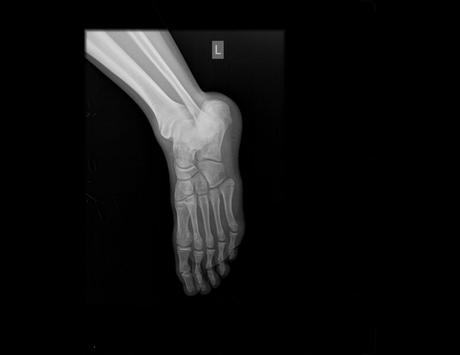

Radiografía anteroposterior y oblicua de pie, donde se observan los siguientes hallazgos:

• Porción distal de tibia y peroné presentan adecuada mineralización ósea, sin evidencia de lesiones líticas o blásticas, ni trazos de fractura.

• Astrágalo, calcáneo y huesos del tarso con densidad ósea normal, sin observar soluciones de continuidad, lesiones líticas o blásticas, sin esclerosis de sus bordes. Adecuada relación entre las estructuras óseas del tarso.

• Se aprecia solución de continuidad de trazo transverso en el quinto metatarsiano a nivel proximal. Resto de los huesos metatarsianos y falanges con adecuada mineralización ósea, sin evidencia de lesiones líticas o blásticas, ni trazos de fractura.

• Articulaciones tarso-metatarsianas, metatarso-falángicas, e interfalángicas presentan espacio conservado y superficies articulares definidas.

• Tejidos blandos con adecuada diferenciación, sin evidencia de alteraciones.

Impresión diagnóstica:

-En el presente estudio que muestra fractura proximal del 5to metatarsiano (fractura de Jones). Resto sin evidencia de alteraciones detectables al momento. A correlacionar con historia clinica del paciente.